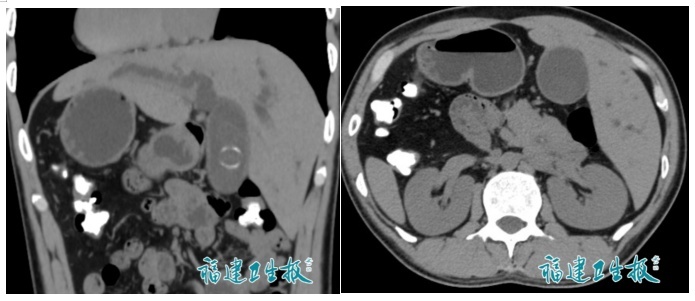

反转的脏器CT影像

陈先生因腹痛、皮肤发黄前往医院检查,检查结果令人意外:不仅查出有胆总管结石,更惊人的是,他的右位心、完全内脏反位,通俗说,就是“五脏六腑像照镜子一样长反了”!